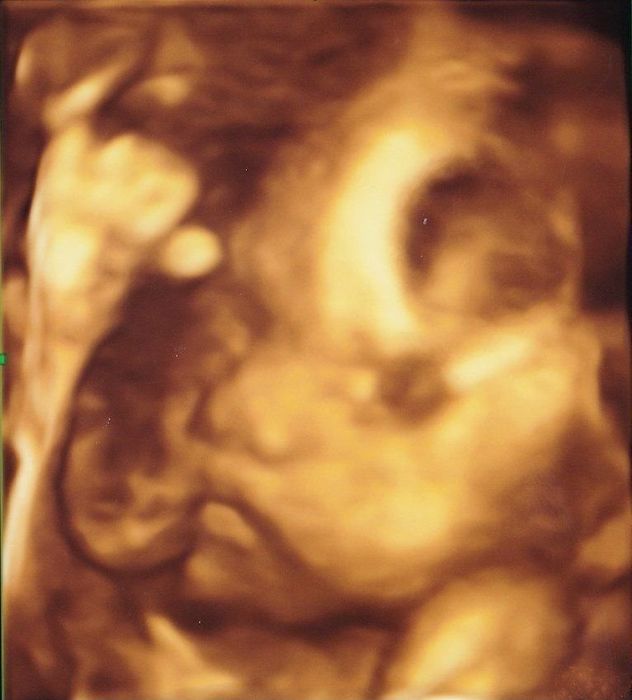

妊娠14週目の4Dエコー写真 初めての4Dのリアル画像にびっくり

D=10.2cm

この検診から4Dエコーでの診断になります。左を向いて、手と足を曲げて赤ちゃんらしい姿が映し出されました。4Dの映像はリアルで、こんなに小さくても手や足がしっかりついていることに生命の神秘を感じました。私もおなかのふくらみを感じるようになり、少しゆるめの服装で過ごすように。軽い風邪をひいたり、肌荒れがひどくなったり、マイナートラブルが目立ってきて、不安を感じることも多かったです。